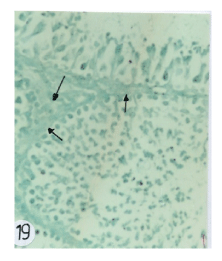

| Figure 19: Photomicrographs of testes sections of rats treated with insecticide mixture of (1/60 of LD50 of chlorpyrifose and 1/200 LD50 of fenitithione) showed signifi cant depletion in the brown granules within the primary stages of germ cells (arrows). |